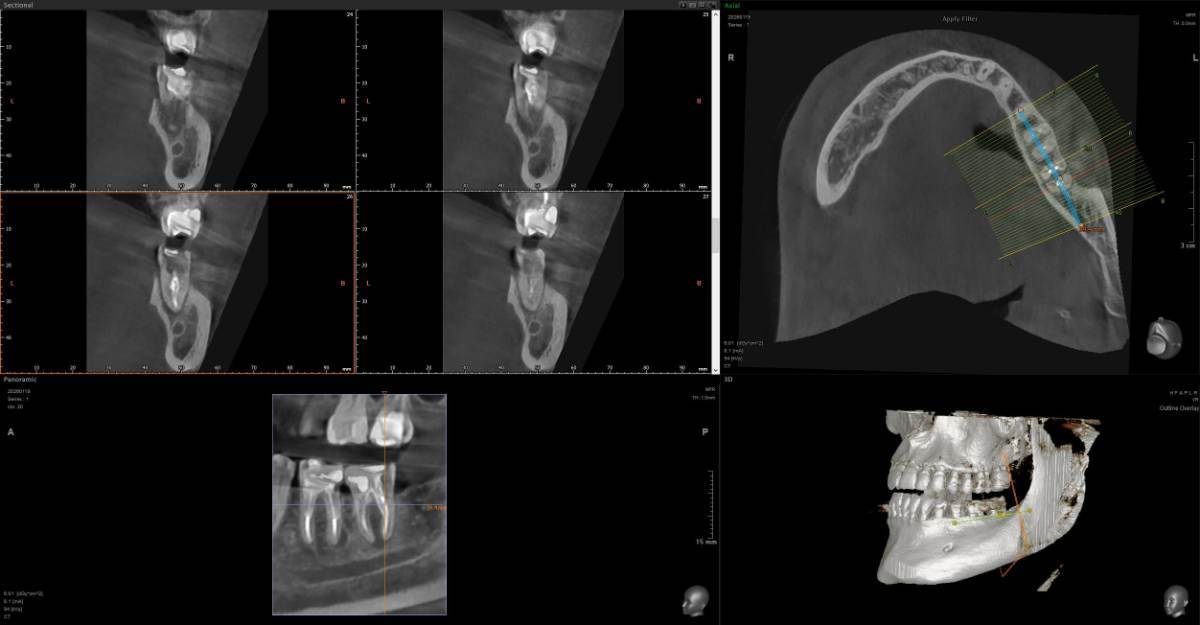

A-V-S Опубликовано 3 марта Поделиться Опубликовано 3 марта Здравствуйте. У меня такая ситуация: В начале января 2026 начал болеть зуб 7ка снизу слева - боль развивалась постепенно - в итоге стало больно жевать. Сделал КТ. Лечащий стоматолог сказал, что это проснулось спящее воспаление, перелечивать каналы зуба сложно - надо сверлить буром и доставать стекловолоконный штифт - надо удалять. В следующие дни открылся свищ и боль ушла. Свищ продолжает быть с периодическим набуханием и сдуванием после выброса гноя белого цвета. Этот зуб лечили с установкой стекловолоконного штифта чуть больше 5 лет назад. Посмотрите, пожалуйста, приложенные снимки и посоветуйте как быть - можно ли перелечить и сохранить зуб ? Ссылка на комментарий

АнтонТЛТ Опубликовано 3 марта Поделиться Опубликовано 3 марта Добрый вечер, лучше выложить несколько срезов этого зуба, либо архив с кт. По представленным снимкам, есть подозрение о наличии трещины между корнями зуба. 1 1 Ссылка на комментарий

red_butler Опубликовано 4 марта Поделиться Опубликовано 4 марта Здравствуйте, Вы выложили не срезы. а реконструкцию. Залейте кт в облако и скиньте сюда ссылка на скачивание Ссылка на комментарий

Гарриевич Опубликовано 6 марта Поделиться Опубликовано 6 марта Не знаю обрадует Вас это или огорчит, но зуб можно сохранить соседний тоже с воспалением кстати 1 1 Ссылка на комментарий

red_butler Опубликовано 9 марта Поделиться Опубликовано 9 марта В 03.03.2026 в 22:49, A-V-S сказал: можно ли перелечить и сохранить зуб ? можно Ссылка на комментарий